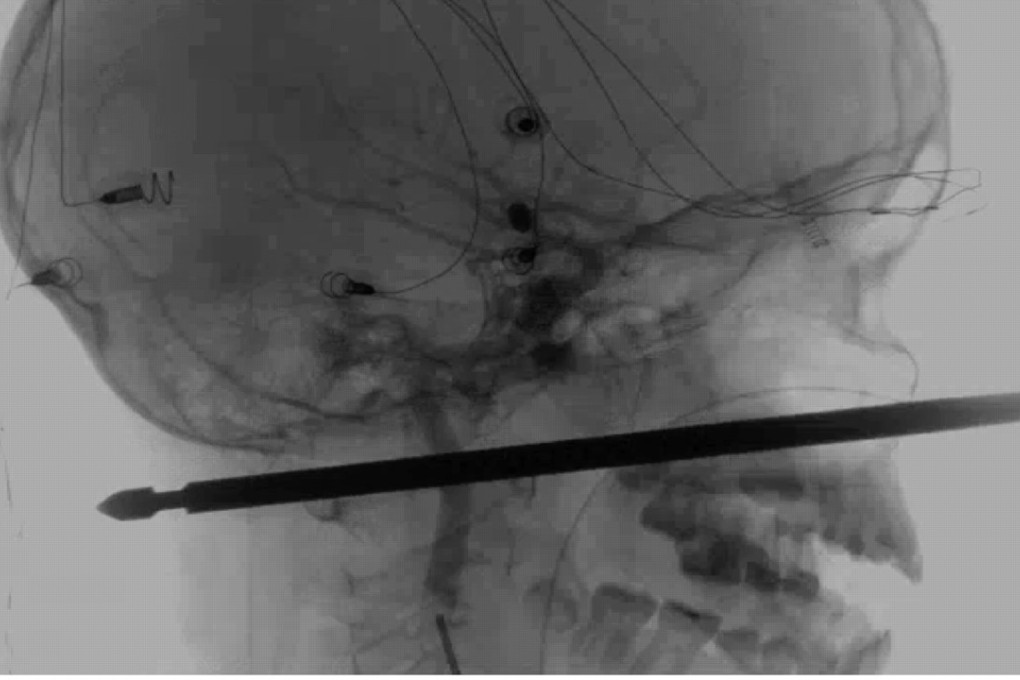

Miraculous survival of US boy Xavier Cunningham, 10, impaled through skull in freak treehouse accident

A 10-year-old American boy was making a remarkable recovery Wednesday after a meat skewer impaled his skull but missed his brain, in what medics called a “one in a million” accident.

Had Xavier Cunningham landed fractions of a centimetre to either side after falling from a treehouse ladder onto the sharp metal spit fixed upright beneath, he may have been severely injured or killed.

“This thing had spared the eye, spared the brain, spared the spinal cord,” neurosurgeon Koji Ebersole, head of the local university health authority, told The Kansas City Star.

I have not seen anything passed to that depth in a situation that was survivable, let alone one where we think the recovery will be near complete if not complete

“It was one in a million for it to pass five or six inches (13-15cm) through the front of the face to the back and not have hit these things,” he added.